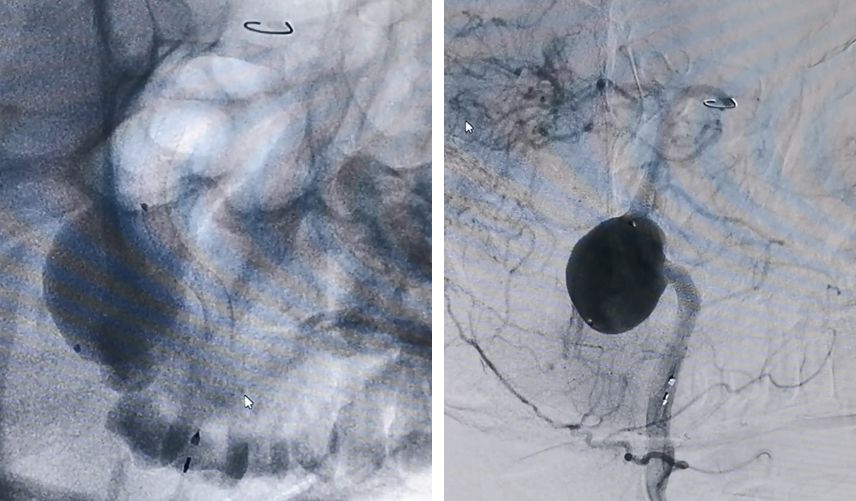

先用Synchro-200携Echelon-10由右椎动脉进入动脉瘤腔,微导管在瘤腔内盘圈,可以在输送弹簧圈的时候使弹簧圈分布更均匀

然后将Marksman微导管通过左侧椎动脉顺利进入左侧大脑后动脉

PED支架沿Marksman进入准备释放

释放PED。由于瘤颈很宽,所以PED需要足够长,动脉瘤远端和近端才能具有足够的锚定力量,防止支架坠入瘤腔内。所以,我们选择了3.25*35mm的支架。支架上端定位在基底动脉中段

PED释放完毕,位置及贴壁良好,左椎-基底动脉血运通畅,未填弹簧圈,即可见到瘤腔内造影剂的滞留,说明支架贴壁良好,起到了良好的重建作用

经右椎动脉逐步填塞大弹簧圈进入动脉瘤(Microplex-18系列),逐步将动脉瘤疏松填塞。期间微导管头端受到弹簧圈阻力,会缓慢回撤,此时不必刻意调整微导管再次深入动脉瘤腔内,因为我们最主要目的不是严密填塞动脉瘤—那是PED的任务—而是闭塞右侧椎动脉

最后,用小弹簧圈完全闭塞右侧椎动脉(PICA以远)